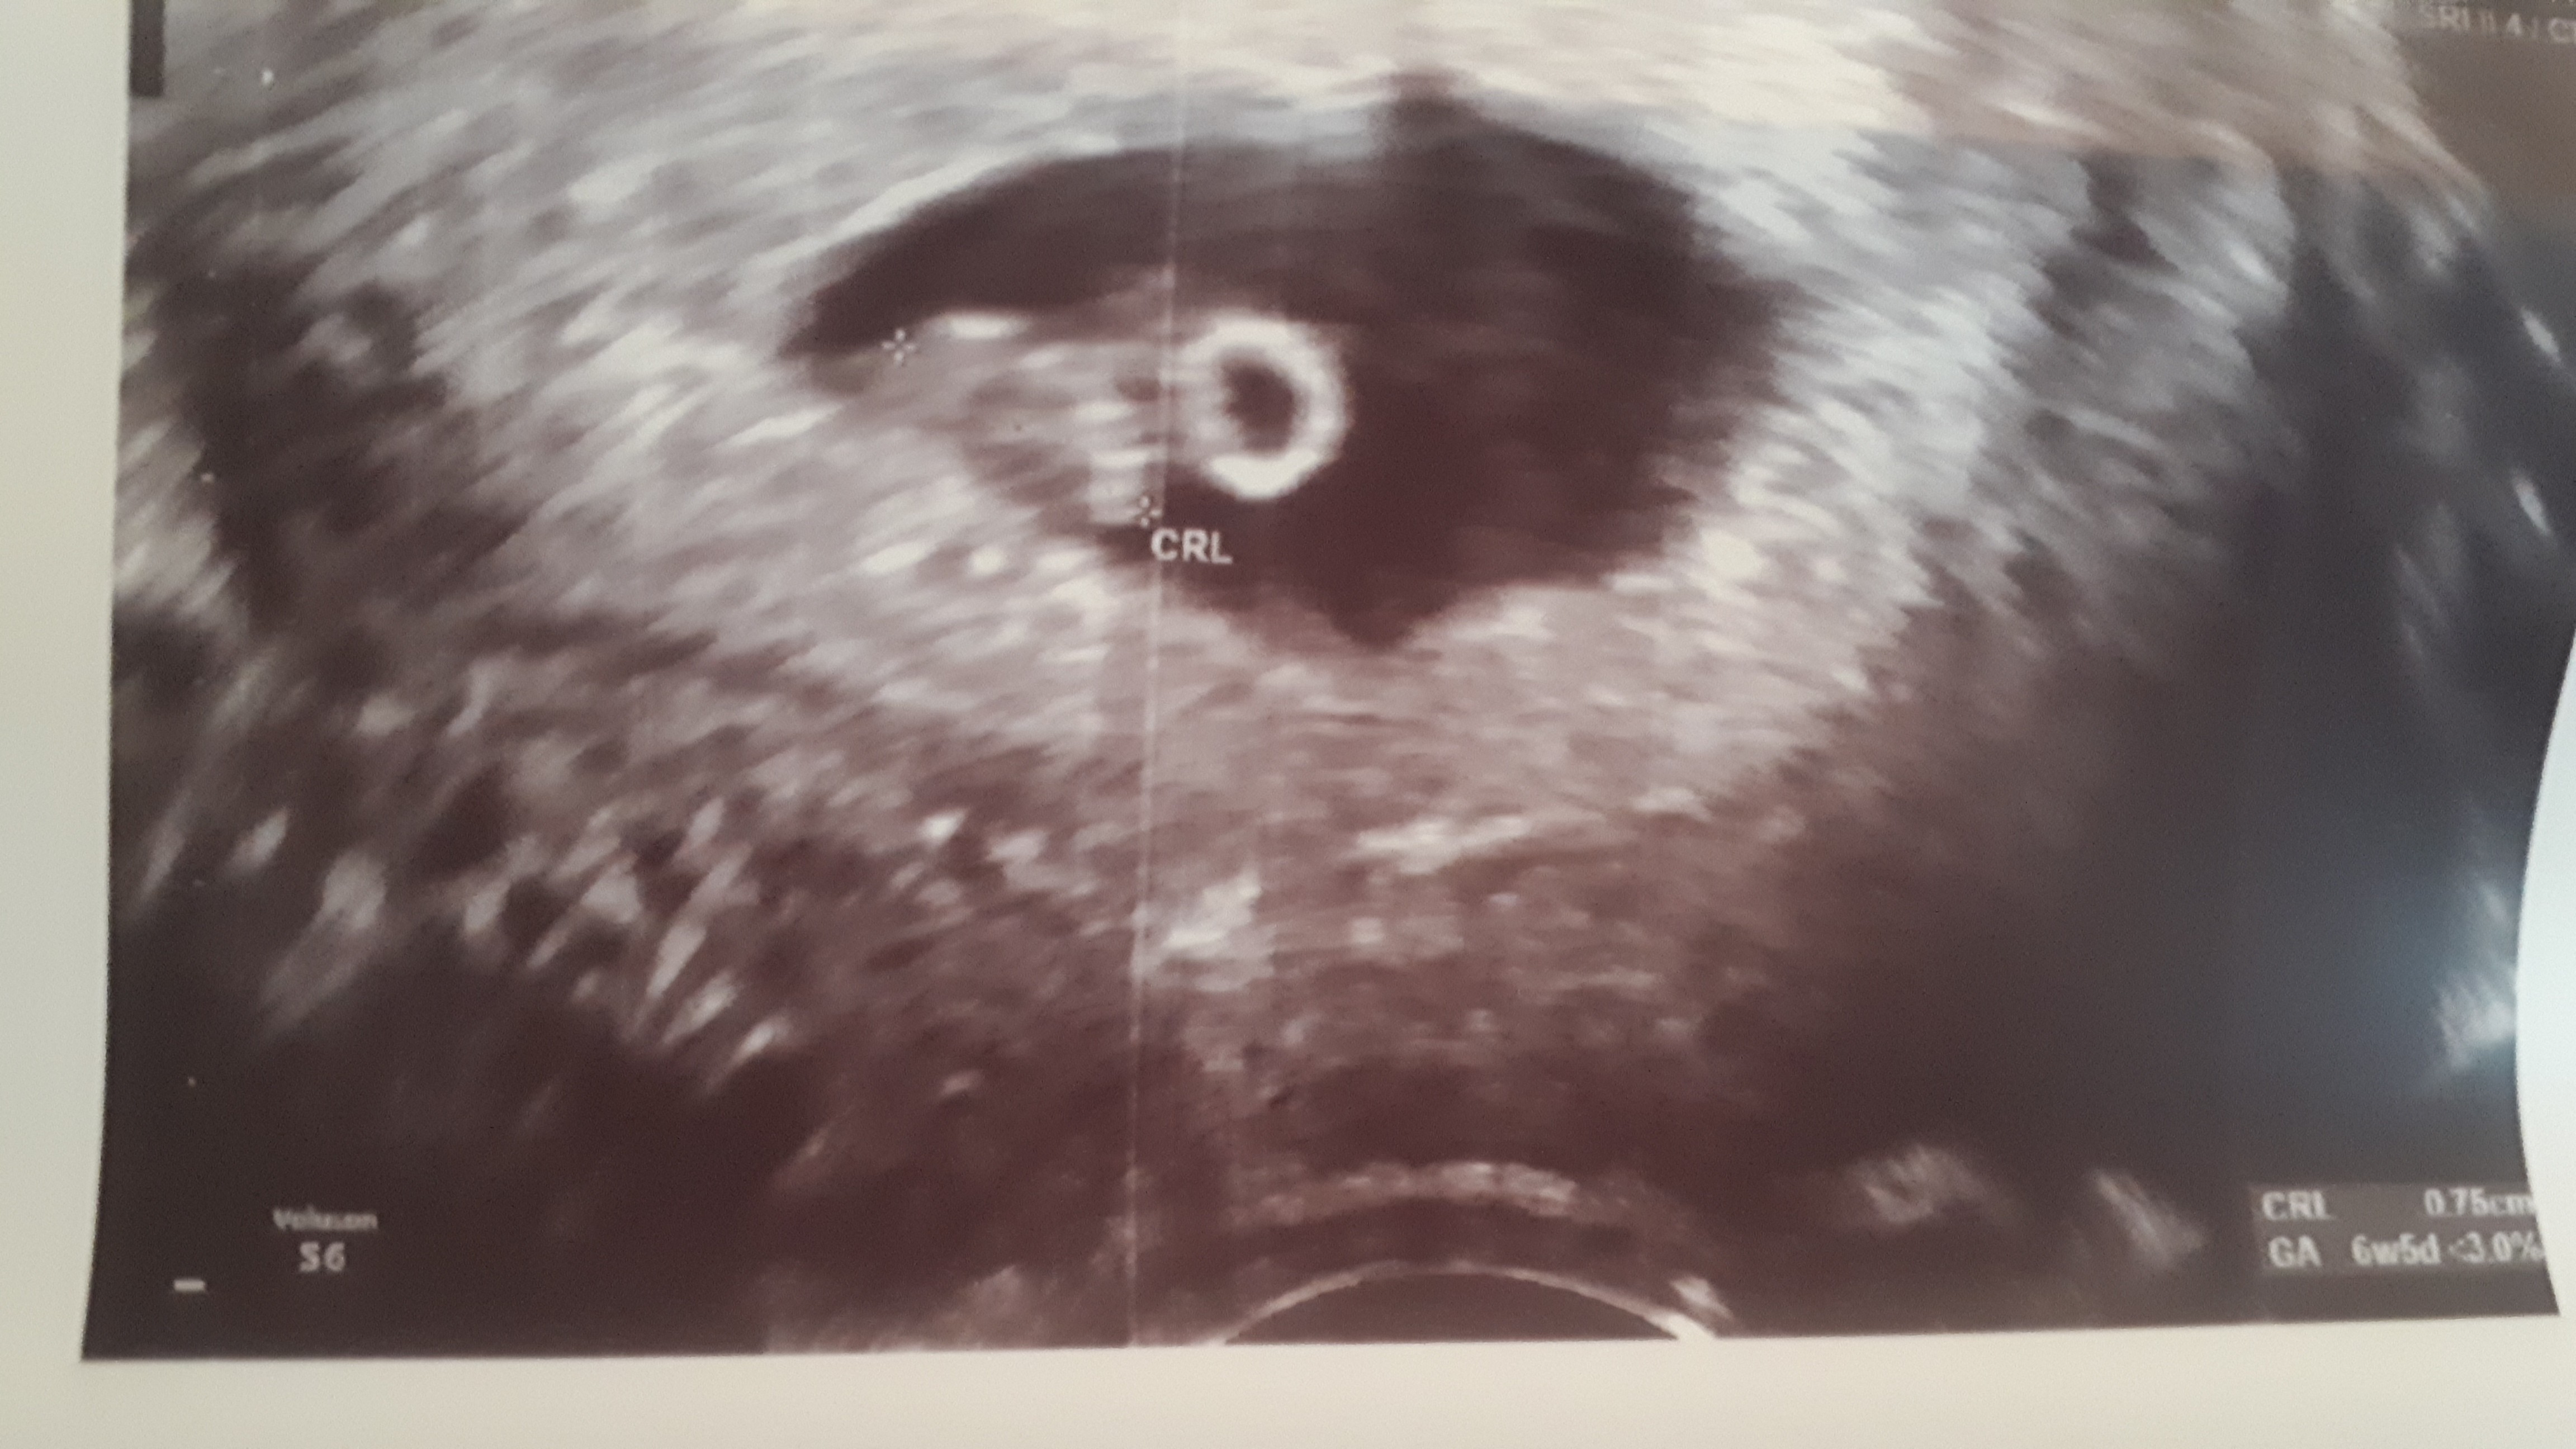

Ooo to już kawał dziecia [emoji3]

tak, wielkosc juz porzadna

a martwilam sie czy wszystko ok, bo jakos dobrze sie caly czas czuje, ale moze naleze do tego waskiego grona szczesciarzy..